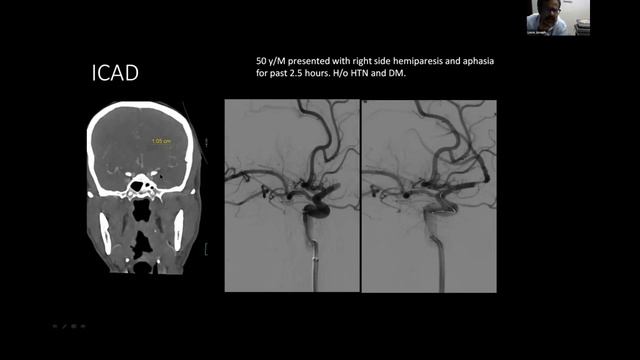

Stroke Syndromes: MCA, ACA, ICA, PCA, Vertebrobasilar Artery Strokes | Pathophysiology